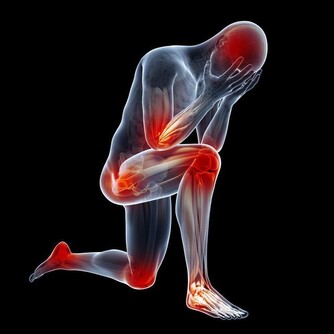

流感(Influenza)是一種由流感病毒引起的急性呼吸道感染,會導致發燒、喉嚨痛、肌肉痠痛、咳嗽、疲勞和食慾不振等症狀。當感染流感時,身體需要額外的營養來支持免疫系統對抗病毒,並加速復原。適當的飲食能夠幫助減輕症狀、提升能量,並促進康復。那麼,流感期間該吃什麼食物?有哪些營養素能幫助身體更快恢復?本篇文章將提供完整的流感飲食指南,幫助您早日恢復健康。